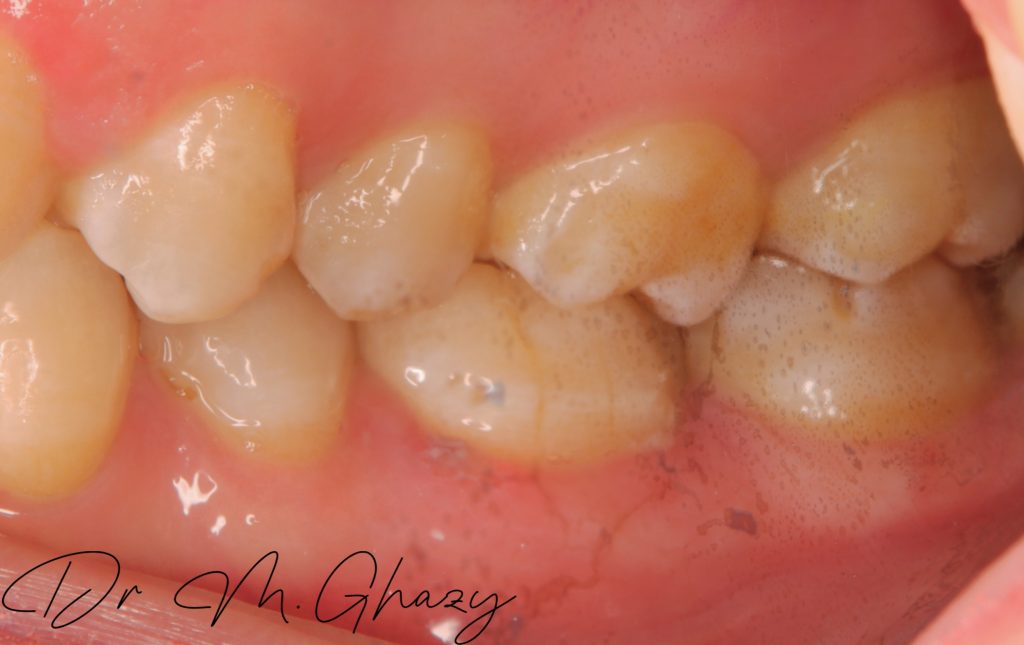

Pre-operatve bite